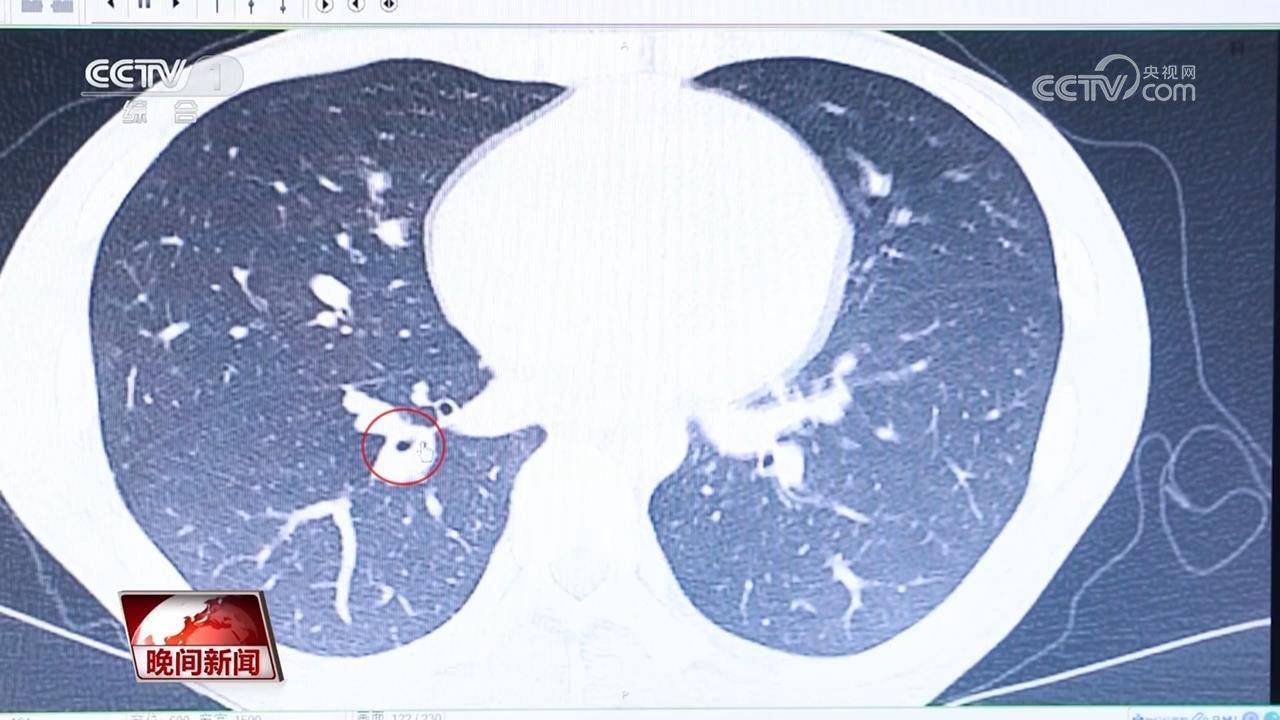

检查发现,小杨右肺下方的气管里日赢配资,藏着一个小小的异物。专家们认为这就是小杨一年来反复发热、咳嗽的病因。

r首都医科大学附属北京世纪坛医院 呼吸与危重症医学科主任 钱进:异物在气道时间比较长,会形成纤维组织的包裹。容易造成气道的阻塞,造成的气道的一个炎症,在这个炎症背景下,异物反倒不容易发现了。